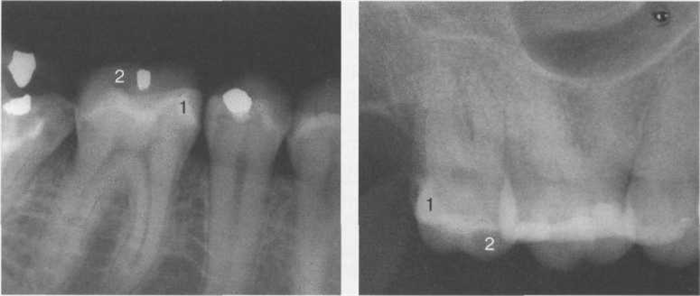

Анатомическое строение челюстей и расположение зубов препятствуют проведению рентгенографического исследования в двух взаимно перпендикулярных проекциях, рентгенография обычно выполняется только в одной проекции, при необходимости могут быть выполнены снимки в косой проекции. На рентгенограммах в прямой проекции губная (вестибулярные и щечные) и оральная (небная и язычная) поверхности зубов дают суммарное изображение, остальные поверхности (аппроксимальные и поверхности смыкания) на рентгенограмме в прямой проекции являются краеобразующими и определяются в виде четко выраженного контура. На рентгенограммах хорошо видны плотные тени эмали, суживающиеся по направлению к шейке зуба. Особенно хорошо виден эмалевый слой аппроксимальной поверхности. На режущих и жевательных поверхностях зубов эмалевый слой с возрастом стирается. Поэтому на рентгенограмме зуба у людей пожилого возраста эмалевый слой в этих отделах отсутствует или выражен в виде тонкой контурной линии. На периапикальном снимке по методу биссектрисы тени щечных бугров премоляров и моляров верхней и нижней челюстей проекционно вытягиваются, так как они отстоят от пленки больше, чем небные и язычные бугры. В результате этого создается впечатление о меньшей плотности и даже отсутствии эмалевого покрова щечных бугров, в то время как на небных и язычных буграх он представлен очень интенсивной тенью (рис. 20.10).

На рентгенограммах тени щечных рогов наслаиваются на тени небных и язычных и раздельно не видны, отчетливо просматриваются лишь тени медиальных и дистальных рогов моляров (рис. 20.11).

Рис. 20.10. Рентгенологическое изображение моляров верхней и нижней челюстей.

1 — небные и язычные бугры; 2 — щечные бугры.

Рис. 20.11. Рентгенограмма второго моляра нижней челюсти.

1 — коронка зуба; 2 — эмаль коронки зуба; 3 — язычные бугры; 4 — небные бугры; 5 — шейка зуба; 6 — корень зуба; 7 — пульпарная камера; 8 — рога пуль-парной камеры (медиальные и дистальные); 9 — дно пульпарной камеры; 10 — корневой канал.